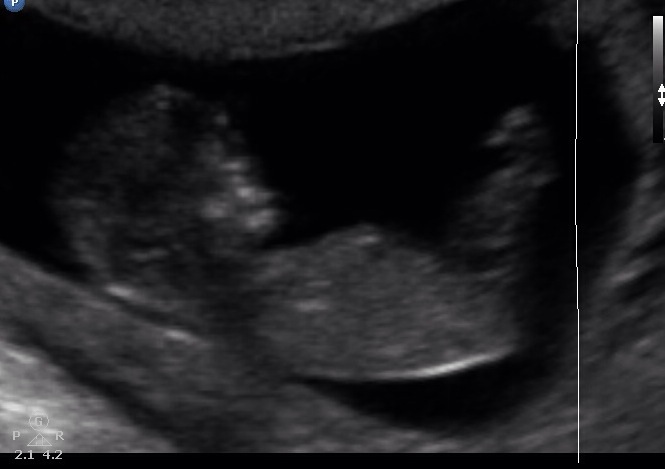

I don't see any clear nub... Slight girl lean from pic 2 but still close to 50/50. What did you see during the live scan?

Slight pink lean from the 2nd pic.

I was going to say girl at first but zooming in there is something on top of that girly nub which could possibly make it a stacked nub = boy. im going 50/50 but dont give up hope just yet